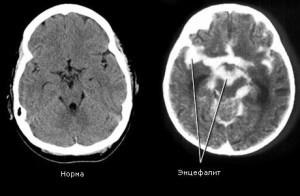

Encefalita la copii apare mult mai frecvent decât la adulți, iar copilul mai mic, cu atât mai dificil este tratat. Imaginea este foarte diverse simptome, cum encefalită termenul nu se ascunde o boala, ci un grup. Să vedem ce este encefalita și cum se întâmplă.

herpetică encefalita

Această formă principală de encefalita la copii este rar, dar cand apare, este nevoie de incredibil de dificil. Boala este al doilea tip de herpes virus, o sursă de distrugere este mucoasa nazală. In plus fata de simptomele encefalitic clasice la nou-nascuti dezvolta paralizie si herpes sepsis, care afecteaza ficatul si creierul.